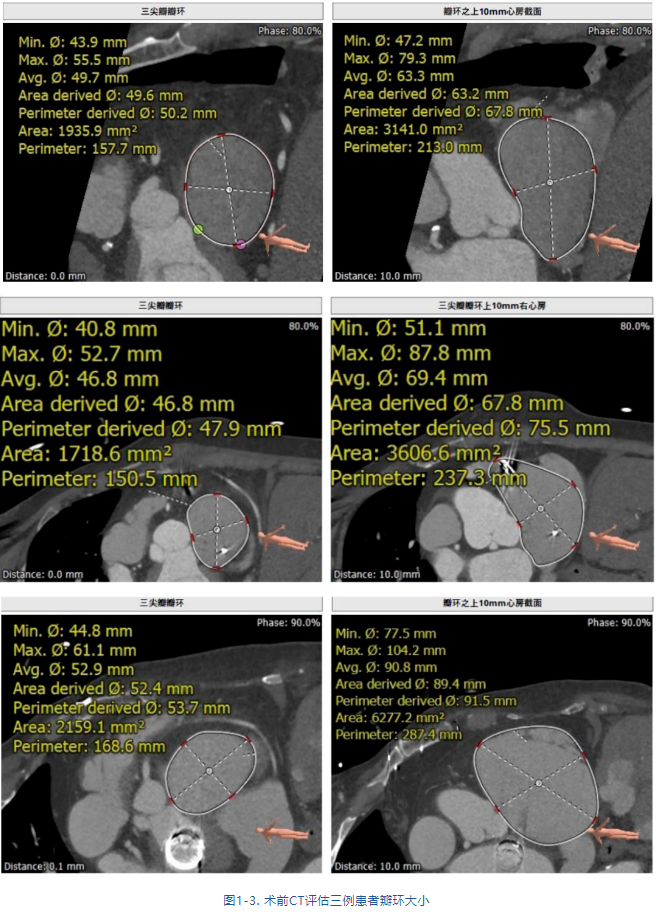

接受治療的是三例重度三尖瓣反流患者,術(shù)前基礎(chǔ)疾病多,均患有嚴(yán)重心律失常,其中兩例患者NYHA心功能Ⅱ/Ⅲ級。結(jié)合術(shù)前CT評估結(jié)果,三例患者的自體瓣環(huán)都較大(圖1-3),最大者平均瓣環(huán)為53.7mm;有一例患者有起搏器植入史,術(shù)中操作有纏繞起搏器導(dǎo)線的風(fēng)險;三例患者入路血管均無嚴(yán)重迂曲和鈣化。經(jīng)術(shù)前討論分析,潘湘斌教授及其團(tuán)隊潘家華教授、朱達(dá)教授、王首正教授以及心超室的駱志玲教授,董念國教授及其團(tuán)隊謝明星教授、尚小珂教授、陳澍教授、鐘禹成教授經(jīng)過討論決定,采用創(chuàng)新的 LuX-Valve Plus經(jīng)血管三尖瓣置換系統(tǒng)對患者進(jìn)行手術(shù)。LuX-Valve Plus是我國自主研發(fā)的經(jīng)血管介入三尖瓣置換系統(tǒng),經(jīng)頸靜脈入路的微創(chuàng)方式可進(jìn)一步降低對患者的創(chuàng)傷。